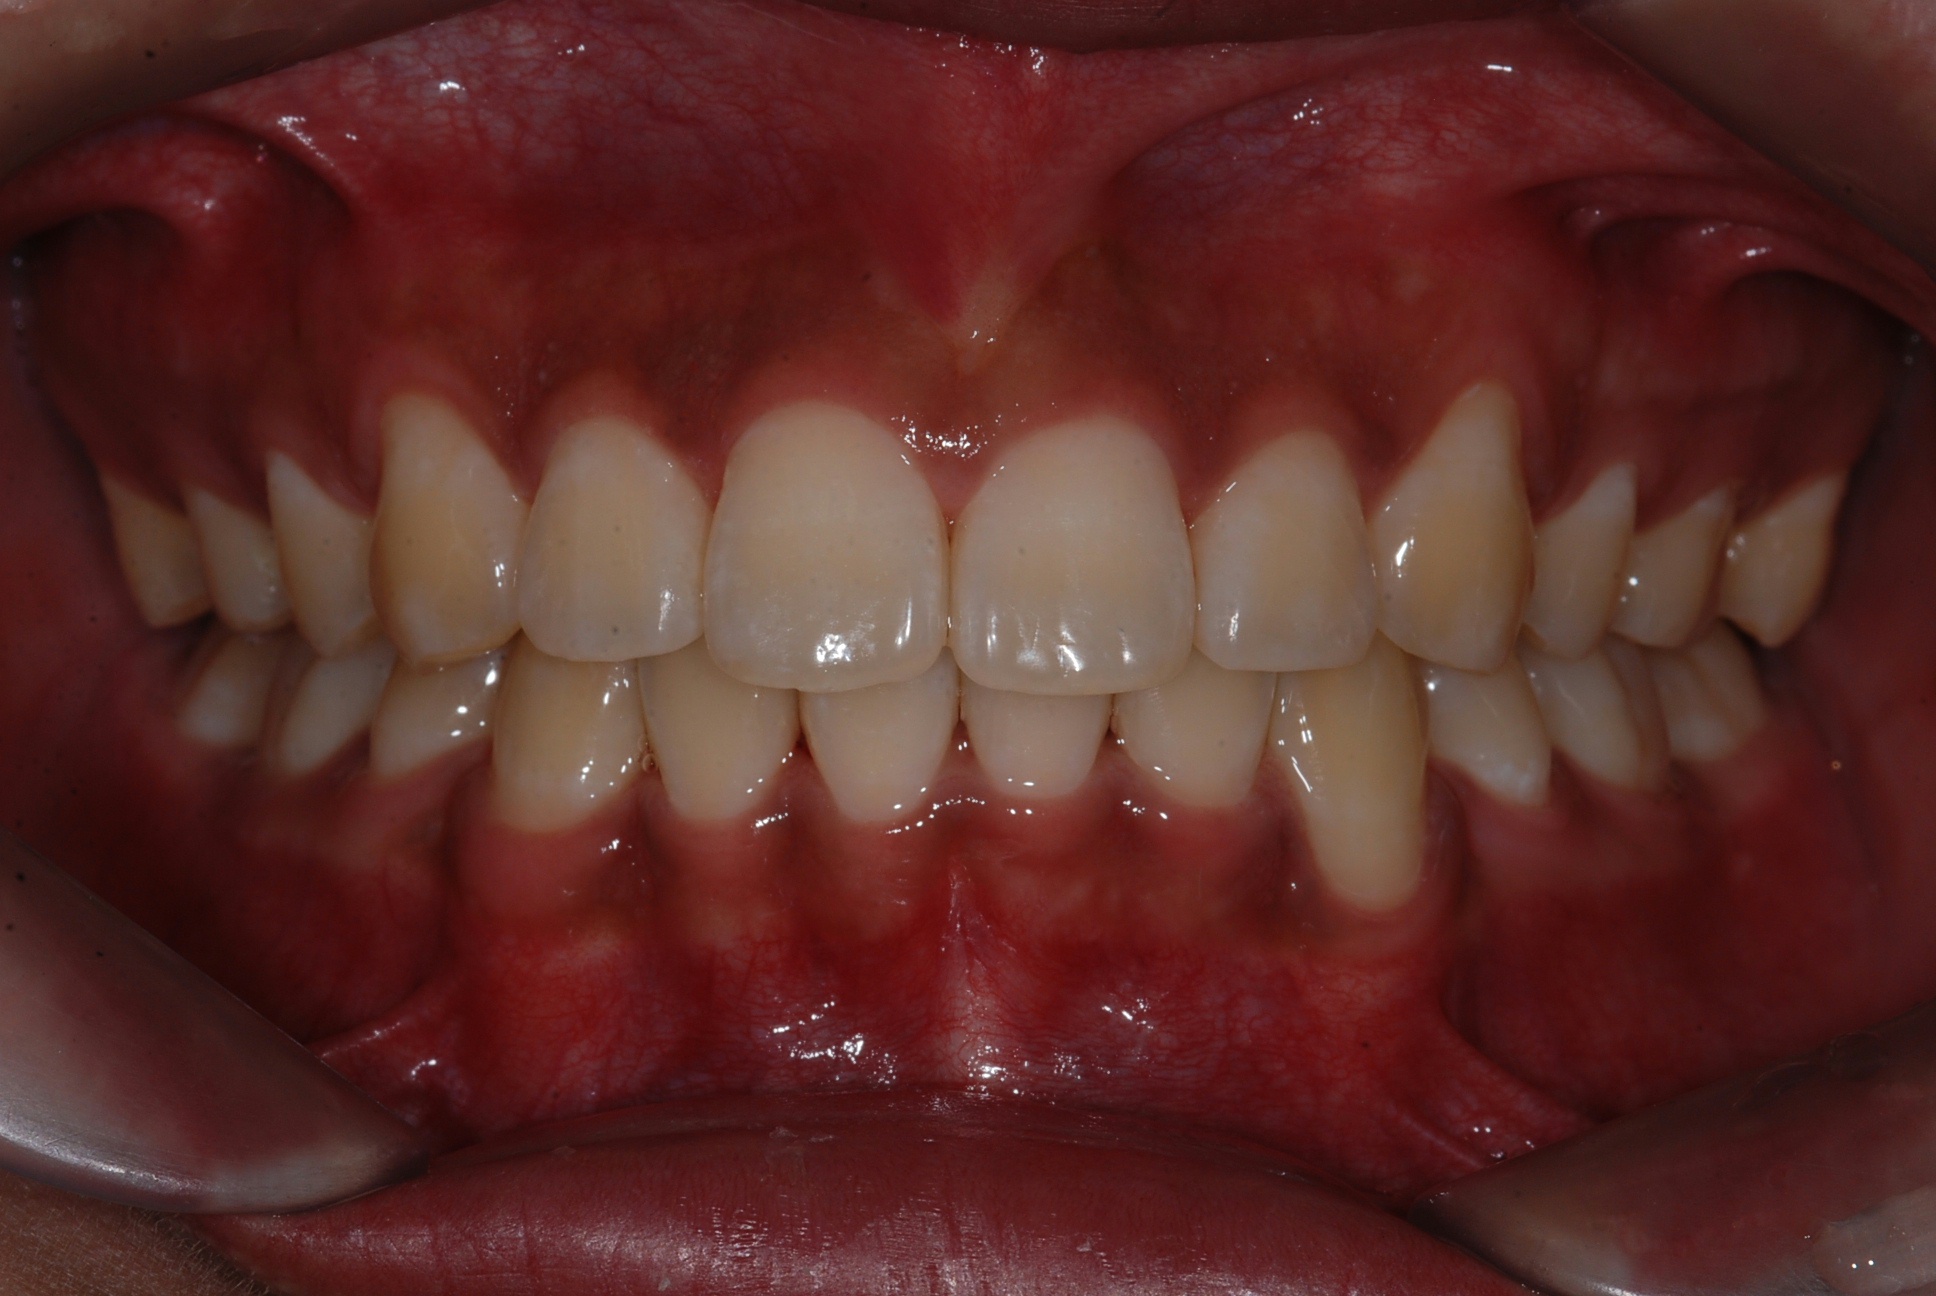

치료 후 사진입니다.